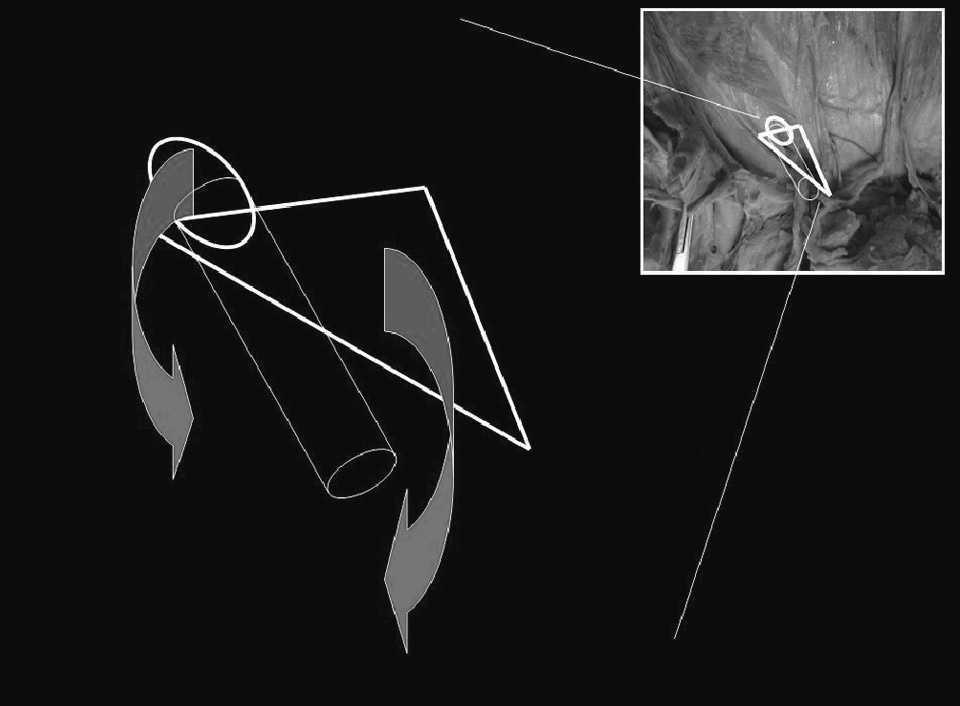

Fig.1.Representación anatómica de la región inguinal.

La mayor parte de las hernias de la región inguinal emergen por el denominado orificio miopectineo4. Este orificio está subdividido por el ligamento inguinal en un nivel superior o suprainguinal y un nivel inferior o infrainguinal. Por el nivel suprainguinal se produce el paso (a través del anillo inguinal profundo) del cordón espermático en el varón o de ligamento redondo en las mujeres. Por el nivel infrainguinal se produce el paso de los vasos femorales. El orificio miopectíneo está completamente cerrado por detrás por la fascia transversalis. Si no consideramos la región infrainguinal y las hernias que por ella emergen (crurales), el espacio suprainguinal tiene dos áreas de debilidad anatómica por donde potencialmente pueden emerger hernias inguinales (fig. 2): el anillo inguinal profundo y la propia fascia transversalis. Sin embargo, a pesar de las altas presiones intraabdominales que se generan en el ser humano con las actividades diarias, no se desarrollan hernias en la inmensa mayoría de los individuos. Esto parece que es debido a los mecanismos fisiológicos de protección de las áreas de debilidad. Los mecanismos fisiológicos de protección son básicamente dos (fig. 3): el primero, denominado “mecanismo de per-siana”5, se activa de forma automática por la propia contracción de los músculos abdominales. La contracción de las fibras inferiores de los músculos oblicuo menor y transverso hace que el borde superior del espacio suprainguinal se aproxime al ligamento inguinal, de esta forma “se cierra” este espacio. El segundo mecanismo es el llamado “esfínter del orificio inguinal interno”6 y consiste en la fijación de los pilares del anillo inguinal al músculo transverso del abdomen, lo cual da lugar a dos acciones cuando este músculo se contrae. La primera acción es la aproximación de los pilares, con lo que se reduce el diámetro del anillo inguinal profundo. La segunda acción es el desplazamiento hacia arriba y hacia afuera del propio orificio. Ambos mecanismos no funcionan de forma independiente, sino que lo hacen de manera simultánea. Los estudios de estos mecanismos se basan en análisis estáticos sobre cadáveres humanos, con la posibilidad de extraer conclusiones sobre la patogenia de la hernia inguinal mediante la extrapolación de sus resultados (de forma teórica) a la situación dinámica de la ingle de un ser humano vivo.

Fig.3.Mecanismos fisiológicos de protección.